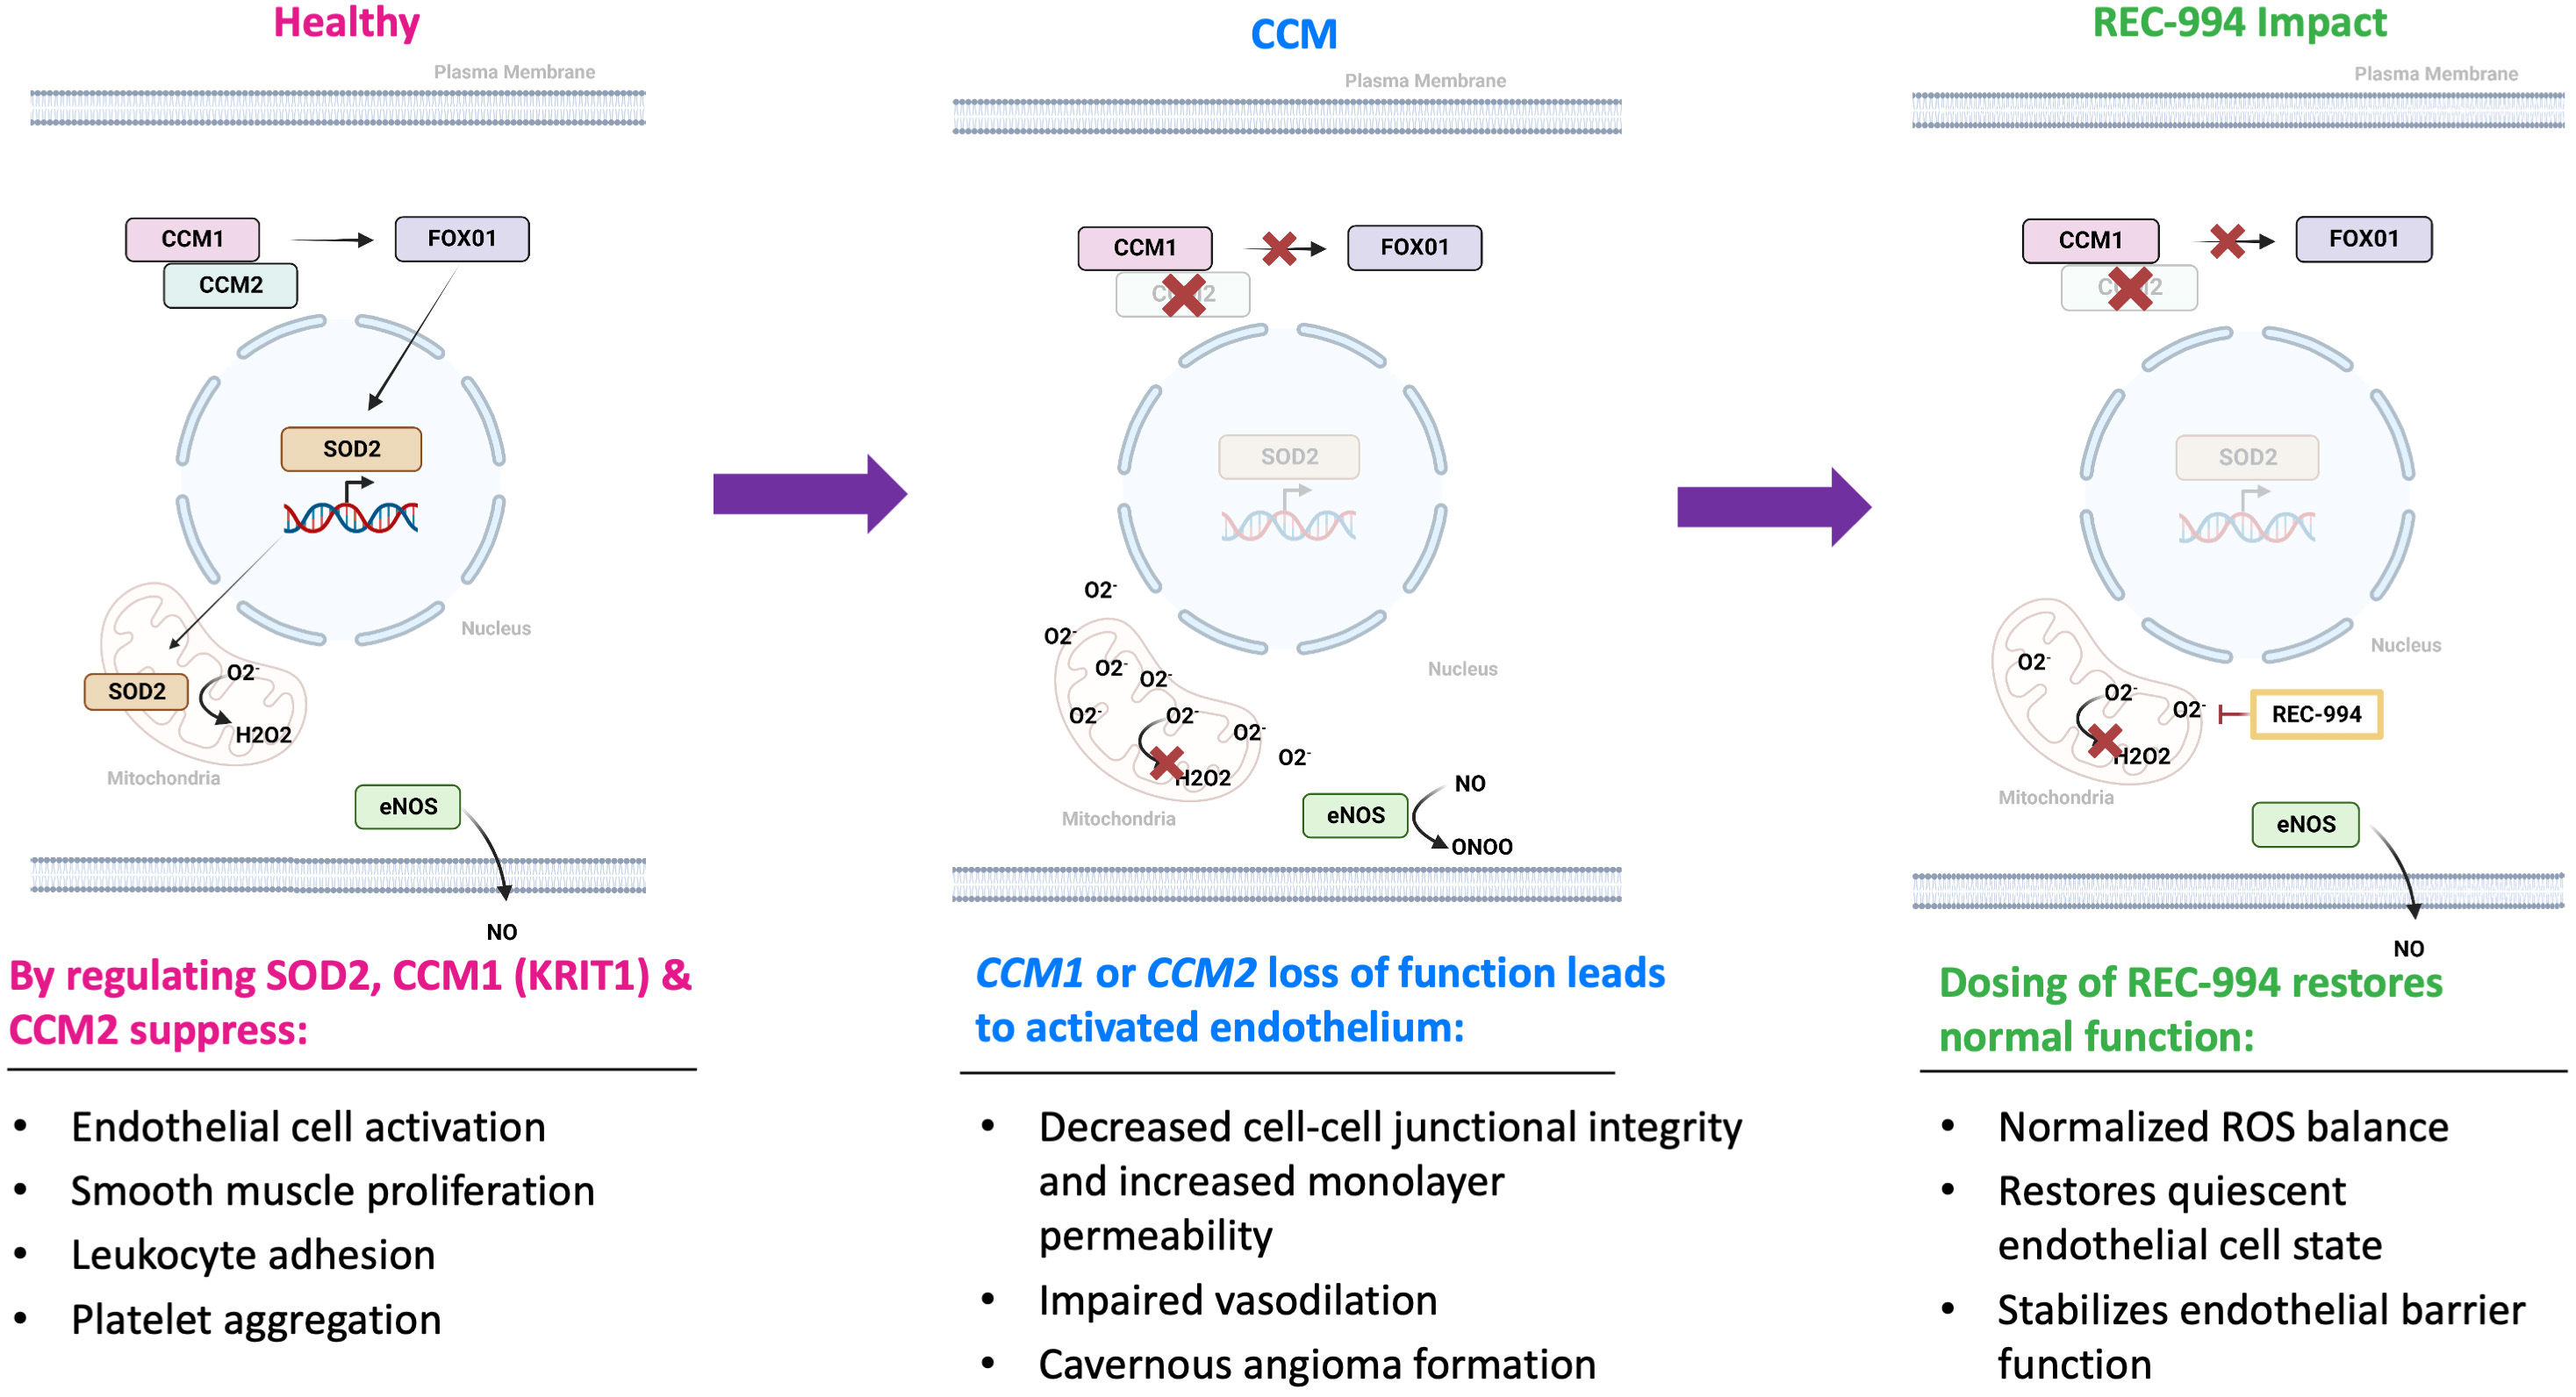

•Five phase 2 clinical-stage programs with multiple upcoming data readouts expected, including REC-994 in cerebral cavernous malformation (CCM) in Q3 2024, REC-2282 in neurofibromatosis type 2 (NF2) in Q4 2024, REC-4881 in familial adenomatous polyposis (FAP) in H1 2025, and REC-4881 in AXIN1 or APC mutant solid tumors in H1 2025

| | What’s more, the signs of AI-enabled point-solutions are already plentiful across our industry: •Protein folding •Scaled protein-ligand interaction prediction •Generative AI for chemistry for tractable targets •The FDA is already discussing the use of LLMs for program review •Major pharma companies are drafting regulatory filings like INDs by LLMs These facts lay out a clear future where efficiencies and improvements across the many current AI-enabled point-solutions will begin to combine into integrated ‘tech-stacks’ and workflows that will result in compounding improvements in our ability to drug historically undruggable targets, understand the underlying networks of biology with increasing fidelity, fast-follow newly validated biology, characterize disease in increasingly robust ways and ultimately deliver more, better medicines to patients to alleviate suffering at scale. The question is no longer whether this sort of future is before us, but when and who will lead it. Looking Back at 2023 and Before Reflecting back on late 2013 when Recursion was founded and how far we have come, it is simultaneously incredible and unsurprising to see where we are today. Recursion was then a Utah-based startup founded by two graduate students and a professor. Our first office was a conference room in the nearby University Research Park and our first laboratory was a converted storage room. Today, Recursion is a multinational, clinical-stage company leading the transition of BioTech into TechBio. We have over 500 employees, five clinical stage programs, one of the world’s largest biological and chemical datasets and two of the largest discovery collaborations in the industry with Roche/Genentech and Bayer. And in 2023, the opportunity ahead feels so much greater than it did in 2013, that in some ways it still feels like we are just getting started. In fact, from an internal perspective, 2023 felt like one of the best years in our history. In 2023 we achieved a lot of important milestones, and a lot of things we’ve been working to build, in some cases for years, really seemed to start hitting their stride, including: Pipeline •Five phase 2 clinical-stage programs with multiple upcoming data readouts expected, including REC-994 in cerebral cavernous malformation (CCM) in Q3 2024, REC-2282 in neurofibromatosis type 2 (NF2) in Q4 2024, REC-4881 in familial adenomatous polyposis (FAP) in H1 2025, and REC-4881 in AXIN1 or APC mutant solid tumors in H1 2025 •Completed a Phase 1 study for REC-3964 in healthy volunteers for the potential treatment of Clostridioides difficile (C. difficile) infection with a favorable safety and tolerability profile •Advanced our RBM39 program in homologous recombination proficient ovarian cancer and other solid tumors to IND-enabling studies •In-licensed a program (Target Epsilon) that emerged from our fibrosis collaboration with Bayer that represents a novel approach to treating fibrotic diseases with compelling early data |